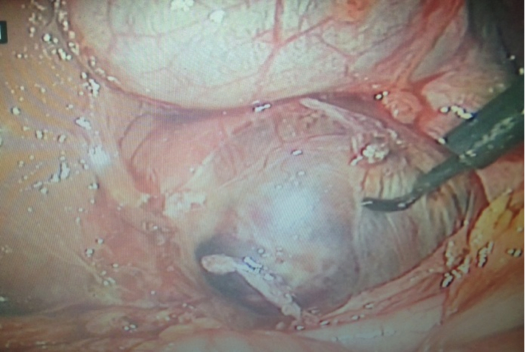

Bệnh nhân nữ 30 tuổi, PARA 1011, tiền sử mổ TNTC ở vòi tử cung bên phải; kinh nguyệt đều, vòng kinh 30 ngày. Bệnh nhân bị chậm kinh một tháng, đau âm ỉ hạ sườn phải 1 tháng, không ra máu âm đạo. Bệnh viện Phụ Sản Hà Nội nghi u nguyên bào nuôi và chuyển đến Bệnh viện Phụ Sản Trung ương. Xét nghiệm β-hCG: 73.047 IU/L; siêu âm Doppler: dưới gan có hình ảnh túi thai d=35mm, chiều dài phôi: 22mm, tim thai (+). Chẩn đoán thai dưới gan. Nội soi: khối thai 3cm nằm ở cạnh phải túi mật, gần tĩnh mạch cửa. Bóc khối thai và cầm máu bằng dao điện và chèn Spongel. Xét nghiệm β-hCG sau 72 giờ: 14.109 IU/L. Giải phẫu bệnh: gai nhau điển hình.

![]() |

| Hình 4. Hình ảnh thai dưới gan khi nội soi (bệnh án 2) |